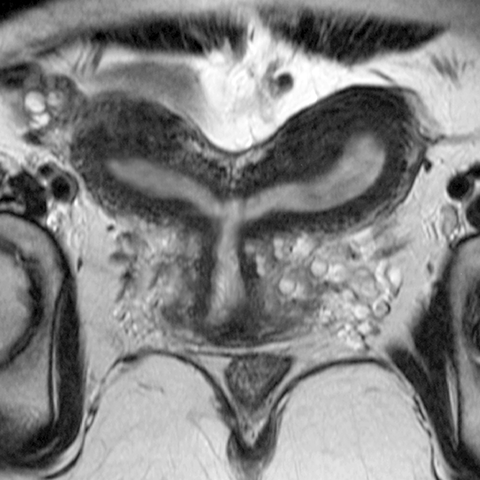

Bicornuate uterus (T2 weighted MR) [2 of 2]